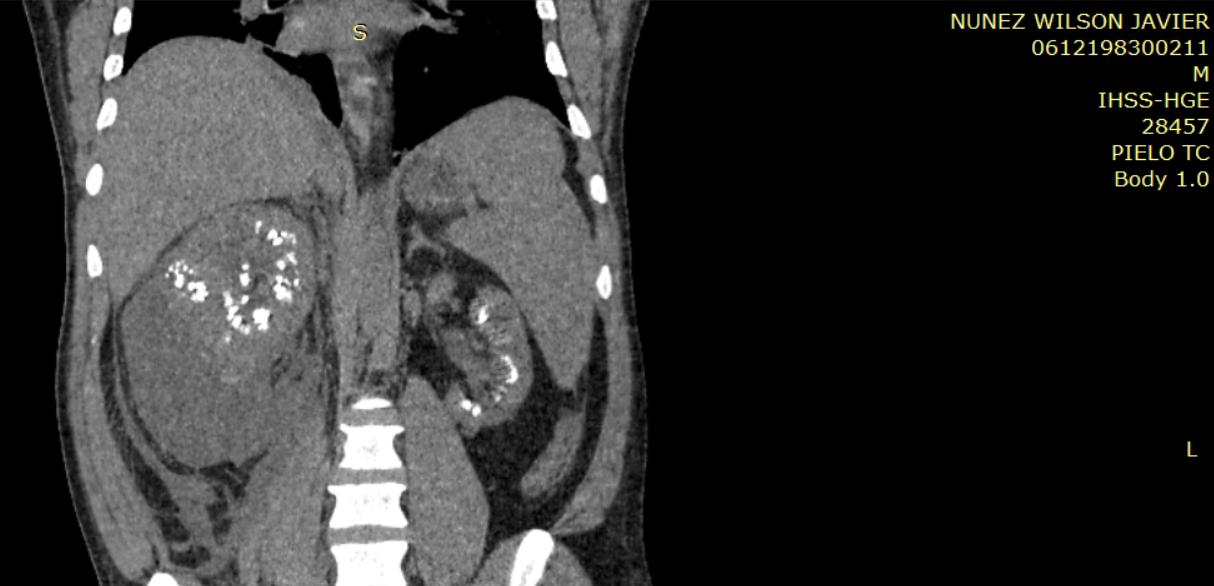

Imagen 6. Imagen de reconstrucción coronal de tomografía abdominal sin contraste (pielotomografia) donde se identifican imágenes hiperdensas en ambos riñones a nivel de pirámides renales, así mismo se observa la presencia de colección perirrenal derecha.

Ambos riñones se observan con presencia de imágenes hiperdensas en sitio anatómico de pirámides renales (valores de atenuación de hasta 1082UH) con presencia de colección perirrenal con densidad liquido (12UH) rodeando riñón derecho. Se observa estriación de la grasa en plano retroperitoneal derecho, extendiéndose hasta fosa iliaca derecha.